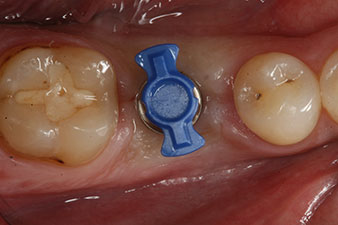

Figura 1: Situación clínica inicial después de la cicatrización del alvéolo de extracción de la pieza 36: la base del hueso es ancha y existe una cantidad suficiente de encía queratinizada.

En el paciente de 28 años con un historial de fumador severo, fue preciso extraer la pieza dental 36 como consecuencia de una recidiva de una periodontitis apical.

Como las piezas dentales adyacentes estaban en su mayoría intactas, el único tratamiento posible para los huecos existentes era un implante.